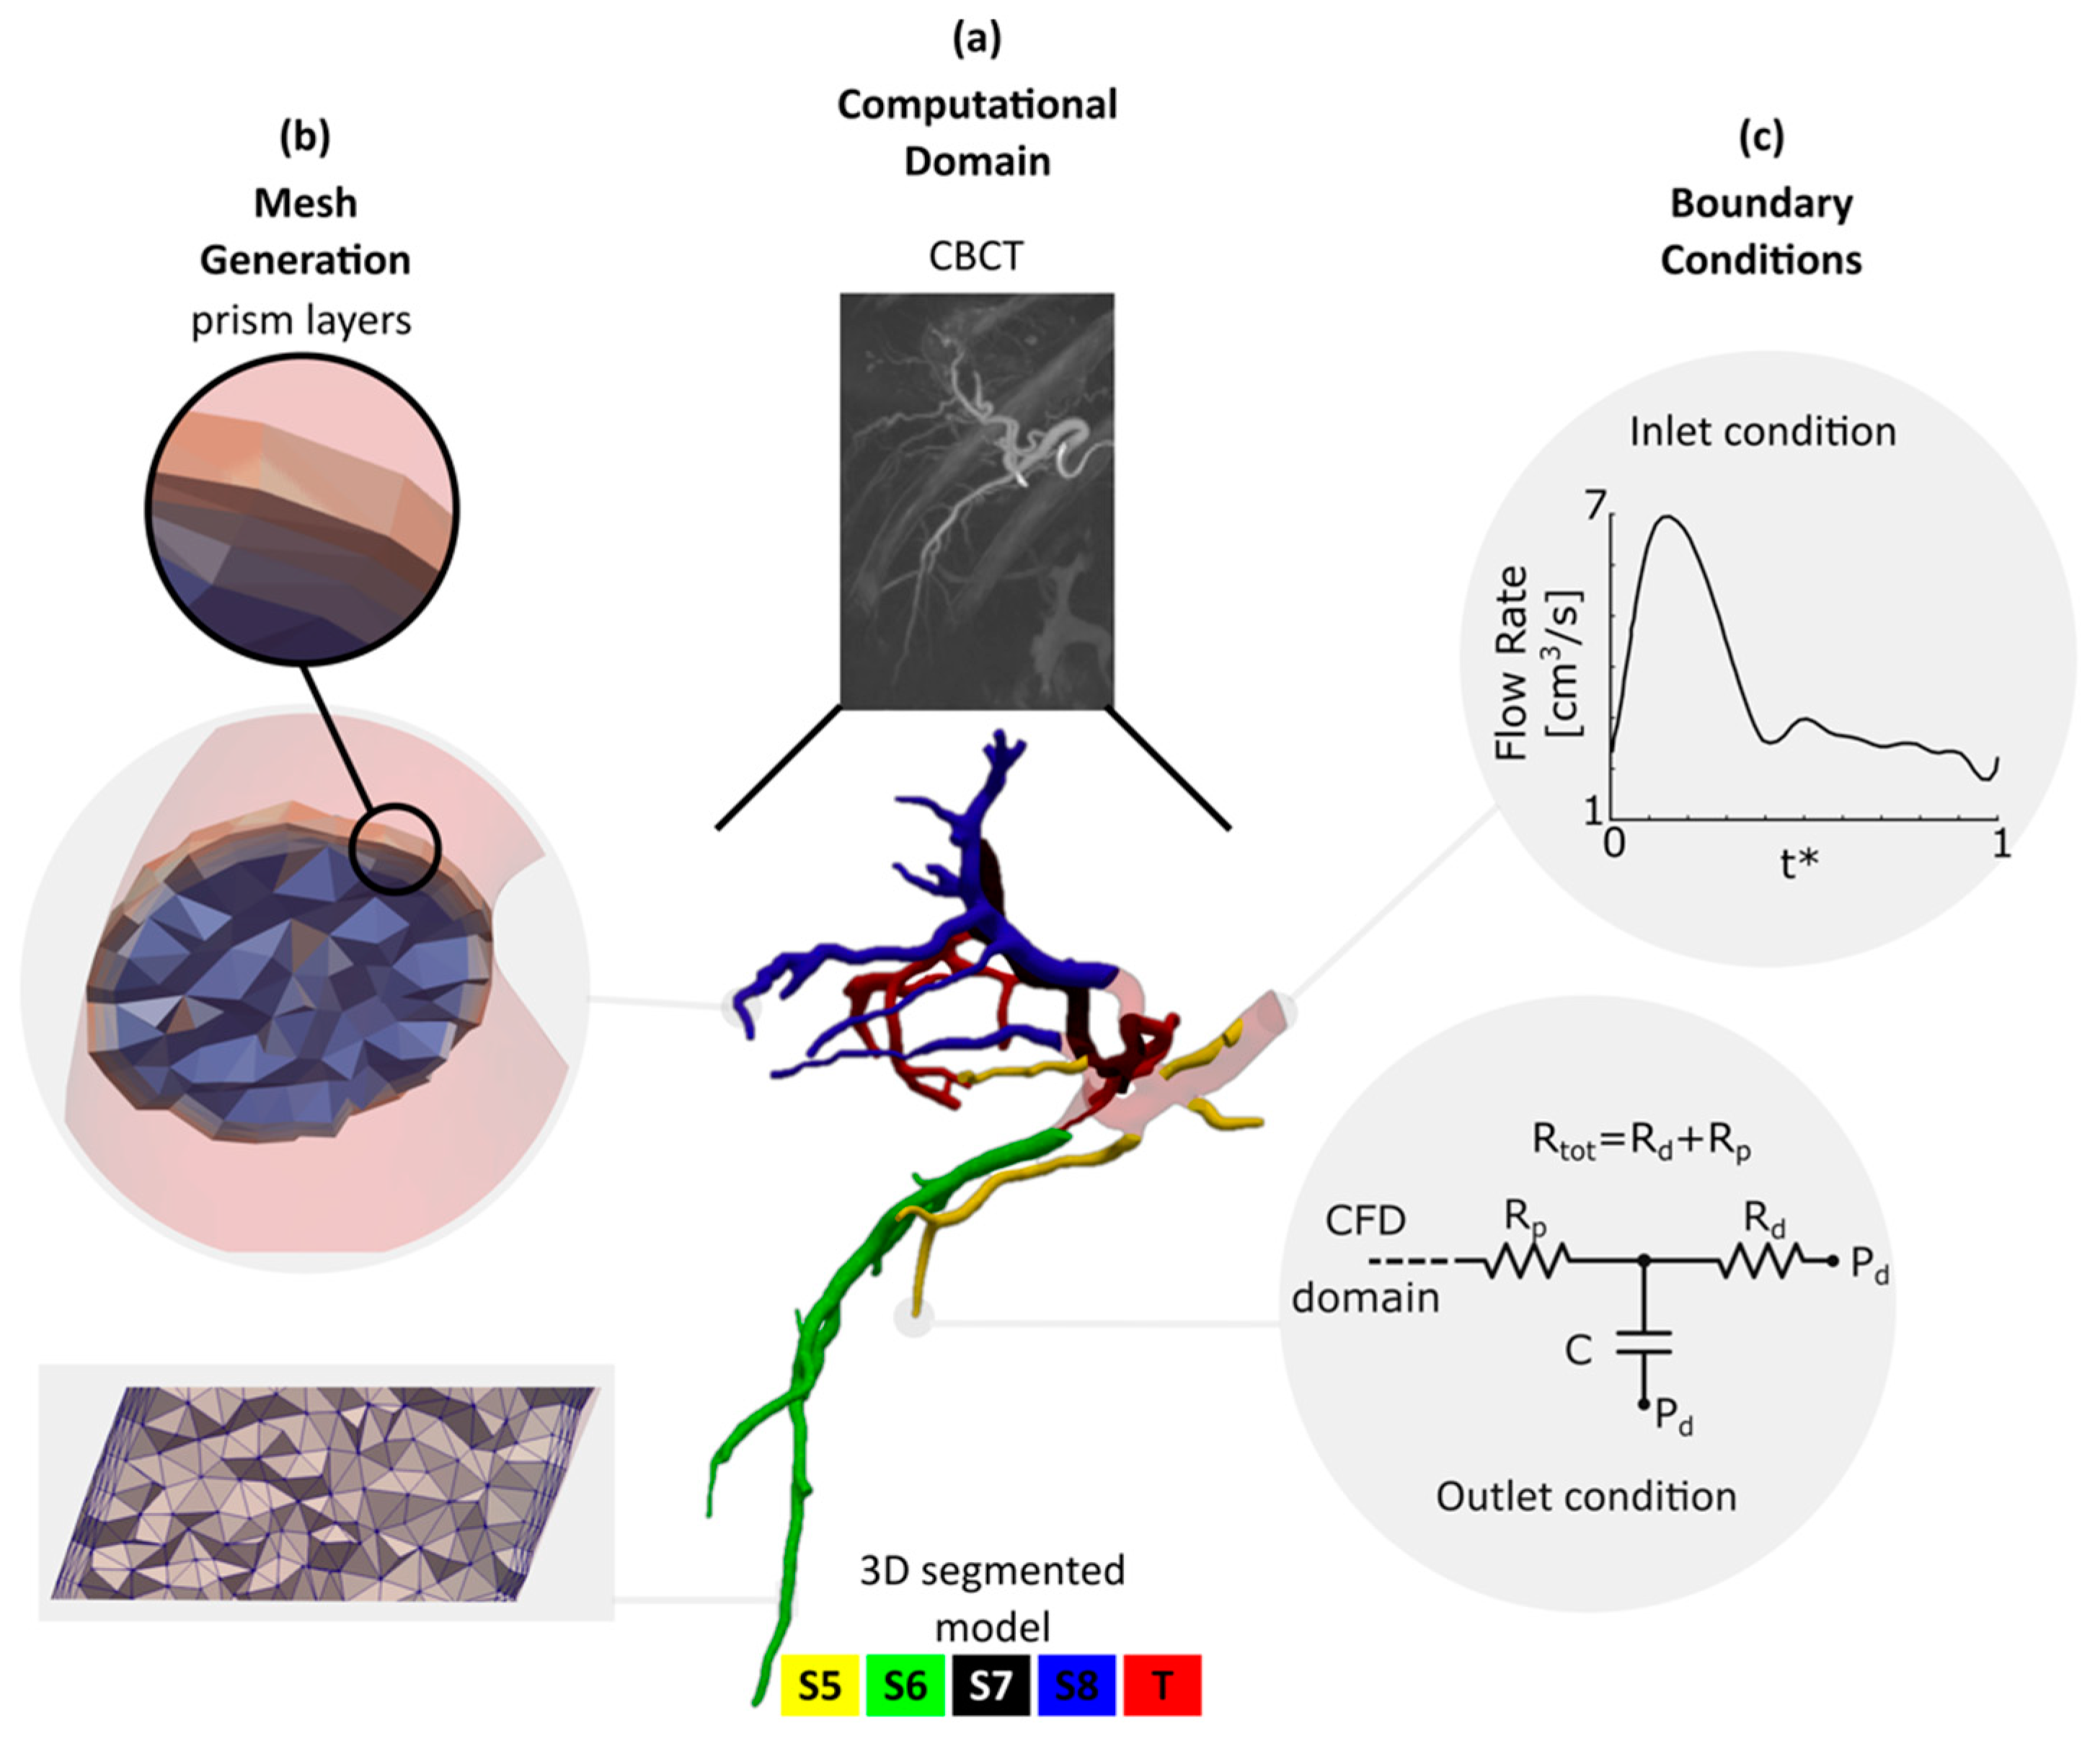

What does CFD stand for in Biomedical Engineering. CFD is the science of predicting fluid behaviour Flow field heat transfer mass transfer chemical reactions etc By solving the governing equations of fluid flow using a numerical approach computer based simulation The results of CFD analyses Represent valid engineering data that may be used for. Structured multi-block grid for an unruptured aneurysm in a cerebral artery a test case used in CFD Rupture Challenge 2013.

Search for PhD funding scholarships studentships in the UK Europe and around the world. CFD is capable of providing valuable hemodynamics which is useful in the clinical assessment of heart performance and the early diagnosis of heart dysfunction 3 6 7. The review then focuses on the applications of CFD in biomedical problems including cardiovascular diseases airflow pattern and aerosol deposition in lungs cerebrospinal fluid flow in brain and for artificial organ design analysis.

Bioengineering Free Full Text Computational Modeling Of The Liver Arterial Blood Flow For Microsphere Therapy Effect Of Boundary Conditions Html